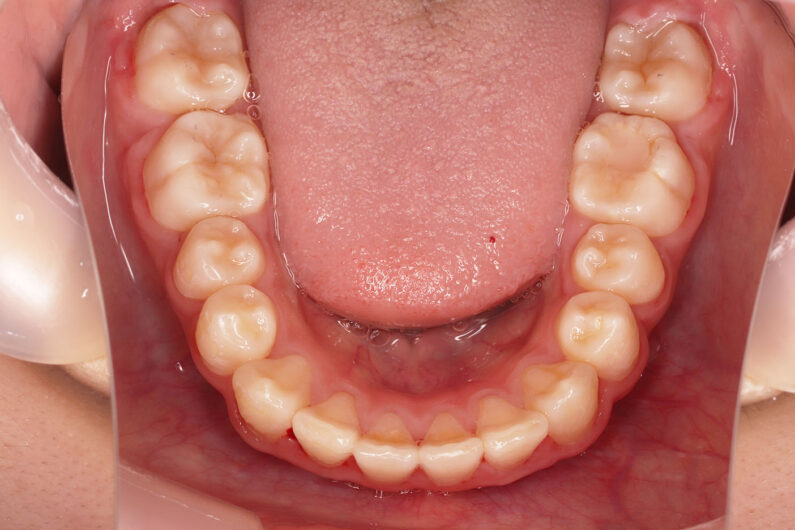

側方歯(犬歯、小臼歯)の生え変わりの時期。 前歯のがたつきを気にされ、小児矯正からの治療を希望されました。 お母様は、矯正治療経験済みですので、治療には前向きで早期治療の必要性を納得されていました。 小児矯正では、永久歯の生え変わるためのスペースを増加させ、がたつきを軽減させることを目的で行います。 残ったがたつきは、全ての永久歯が生え変わってから、本格矯正(マルチブラケット装置での治療)で改善しています。 比較的、叢生量は少ないため、本格矯正は非抜歯にて配列しました。

マルチブラケット 動的治療期間 2年6か月 調整回数16回 特に問題もなく、保定後も安定しています。